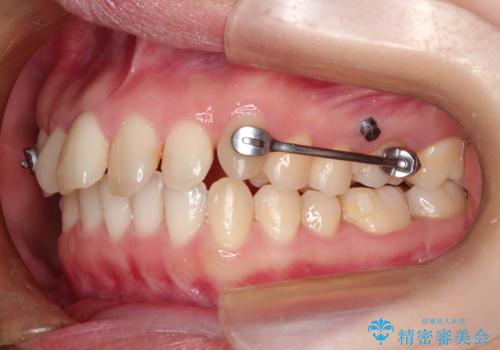

奥歯の嚙み合わせのズレを改善するにあたり、カリエールディスタライザーという装置を併用することで治療期間の短縮を図りました。

カリエールディスタライザーは臼歯の位置関係において理想とのズレが多い場合に有効となります。